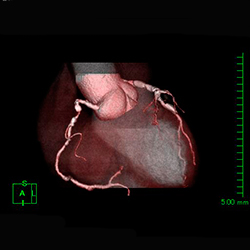

| 血管の中に造影剤を注入して脳、心臓、肝・胆道・膵、腎、四肢などの血管を造影診断、治療します。 心臓を中心とし検査を行う装置と腹部を中心とした検査をおこなう装置(IVR-CT)にて検査、治療をおこなっております。 心臓検査ではバイプレーン(2管球)装置のため少ない造影剤で検査を受けることができます。また腹部装置は80列CTとの組み合わせのためより高精細な画像が収集でき3Dガイド下にて検査・治療を行っています。 | ||||||

▲冠動脈狭窄 治療前

▲冠動脈狭窄 治療後 |